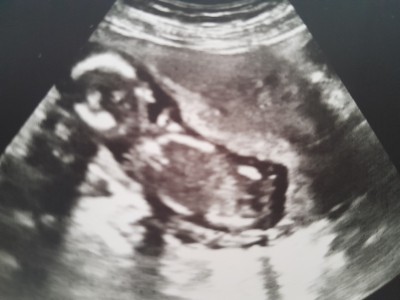

Arkadaşlar anlayan var mi acaba

image

saglıkla kucsgına al cnm erkek

Pek anlamam ultrasondan ama erkek gibi sağlıkla kucağına alırsın inşallah ❤️

Bencede erkek oğlumun ulturason fotorafina benzedi